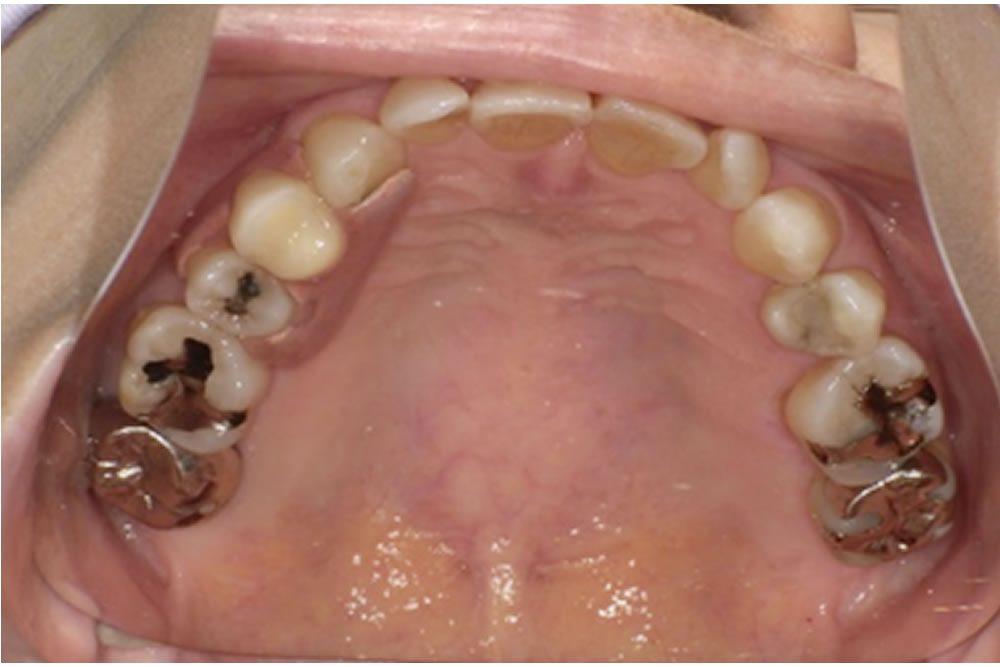

義歯の設計では、口腔内の形態に合わせて、床の前方を小さく・後方を大きめにするなど細かな工夫を行い、装着時の違和感が少しでも軽減されるよう調整しました。

製作したミラクルデンチャー

| 治療費用 | ミラクルデンチャー 右上4 220,000円(税込) |

| 治療期間 | 上顎義歯 2ヵ月(4回) |